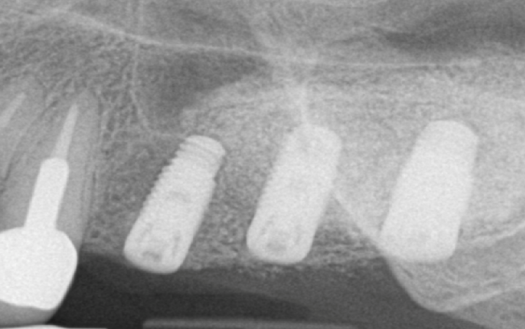

Σε περιπτώσεις όπου τα δόντια έχουν χαθεί πριν αρκετό καιρό, δεν υπάρχει επαρκής ποσότητα οστού για να τοποθετηθεί ένα εμφύτευμα. Αυτό συμβαίνει αρκετά συχνά, στην πίσω περιοχή της άνω γνάθου, λόγω της επέκτασης του ιγμορείου μετά την απώλεια των δοντιών. Σ’ αυτή την περίπτωση πραγματοποιείται ανύψωση του ιγμορείου και τοποθετείται οστικό μόσχευμα για να δημιουργηθεί οστό για την τοποθέτηση του εμφυτεύματος

Πολλές φορές παρατηρούνται ελλείμματα στην άνω και κάτω γνάθο με αποτέλεσμα να μην υπάρχει επαρκής ποσότητα οστού για να τοποθετηθούν εμφυτεύματα. Για να διορθώσουμε αυτό το πρόβλημα πραγματοποιούνται τεχνικές ανάπλασης με οστικά μοσχεύματα και μεμβράνες κολλαγόνου. Κατ’ αυτόν τον τρόπο τα ελλείμματα γεμίζουν και τα εμφυτεύματα μπορούν να τοποθετηθούν σωστά και να διατηρηθούν για πολλά χρόνια.